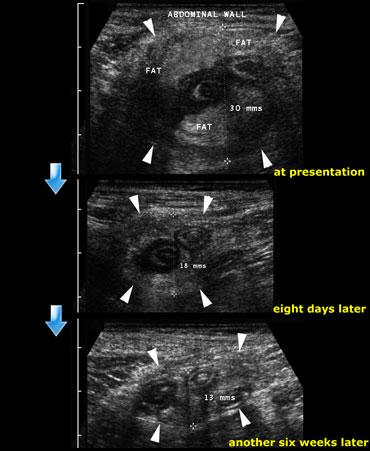

Quá trình thoái triển của đám quánh ruột thừa: Tại thời điểm nhập viện, tám ngày sau và cuối cùng là sáu tuần sau đó.

Đám quánh ruột thừa

Những bệnh nhân nhập viện muộn có thể biểu hiện với một khối sờ thấy được và viêm phúc mạc tương đối nhẹ.

Ở những bệnh nhân này, thường có tốc độ máu lắng (ESR) cao, siêu âm cho thấy một khối lớn gồm mỡ không thể đè xẹp bao quanh ruột thừa, xen kẽ với các dải giảm âm.

Những bệnh nhân này được chẩn đoán là ‘đám quánh ruột thừa’ và thường được điều trị bảo tồn vì phẫu thuật viên biết rằng cắt ruột thừa trong những trường hợp như vậy là khó khăn về mặt kỹ thuật hoặc thậm chí không thể thực hiện được (9).

Bên trái là hình ảnh của một nam giới 35 tuổi với tiền sử đau bụng hố chậu phải kéo dài 10 ngày.

Khám lâm sàng phát hiện một khối sờ thấy được.

Không có bằng chứng viêm phúc mạc.

Trên hình ảnh phía trên, siêu âm cho thấy một khối viêm lớn không thể đè xẹp bao gồm ruột thừa viêm, mạc treo và mạc nối lớn.

Bệnh nhân được điều trị bảo tồn.

Siêu âm theo dõi sau 8 ngày và 6 tuần tiếp theo vẫn còn một số bất thường tồn dư.

Bệnh nhân hoàn toàn không còn triệu chứng.

Không có triệu chứng tái phát và bệnh nhân không phải phẫu thuật.